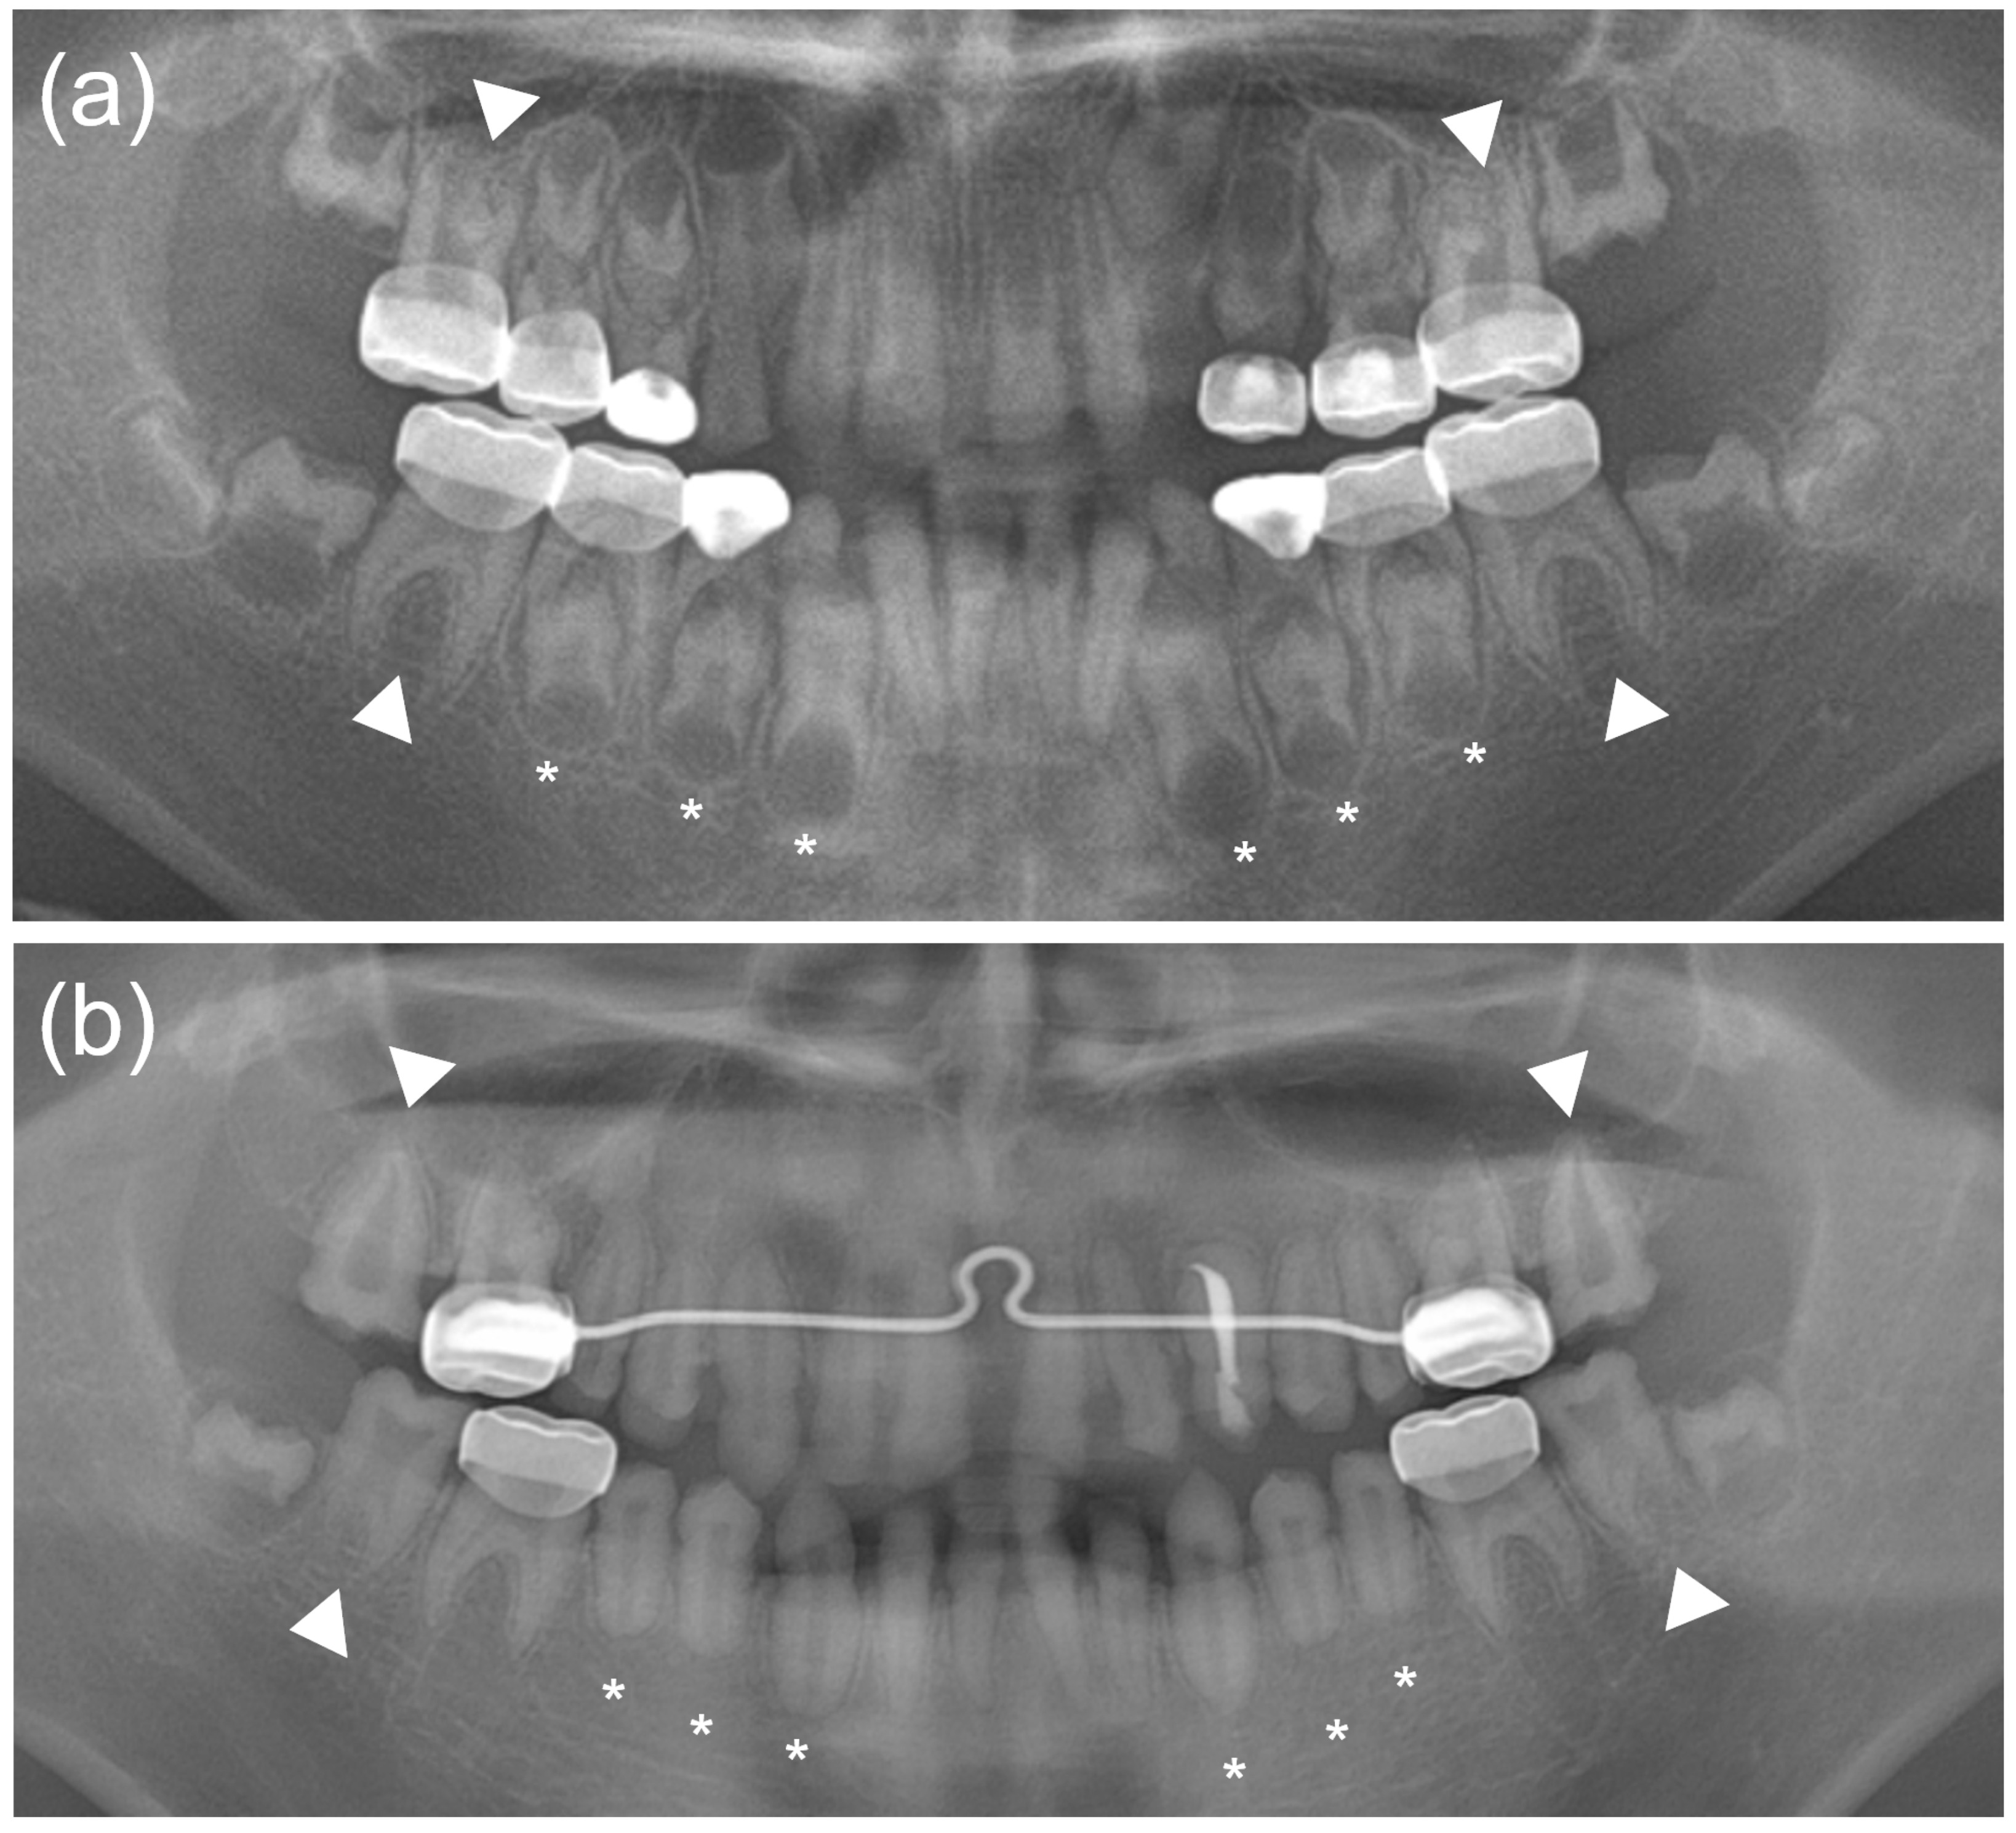

A Novel De Novo SP6 Mutation Causes Severe Hypoplastic Amelogenesis Imperfecta